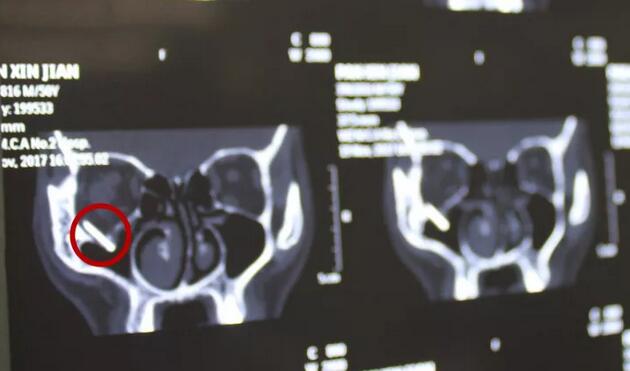

上周一,刘先生骑电动车回家时,在路上遇上车祸,在当地医院,刘叔叔进行了初步的清创缝合处理后。拍了头部的CT才发现刘先生眼眶内竟然有一块类似铁片的巨大异物!

福州眼科医院李谦益主任接诊后,经过详细检查后发现:刘先生虽然眼部周围的外伤已经基本缝合,但是CT显示眼眶内存留的异物巨大,情况比较紧急。李谦益主任随即组织福州眼科医院眼眶病科里医疗团队,进行多次会诊讨论病情后制定了手术医治方案。在11月21日下午,为刘先生施行了眼眶内异物取出的手术,因为前期的详尽准备,手术不到一小时就顺利完成,李谦益主任不仅为刘叔叔顺利取出了巨大异物(玻璃板),还为其保住了视力与光明。